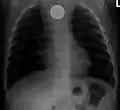

A coin seen on AP CXR in the esophagus